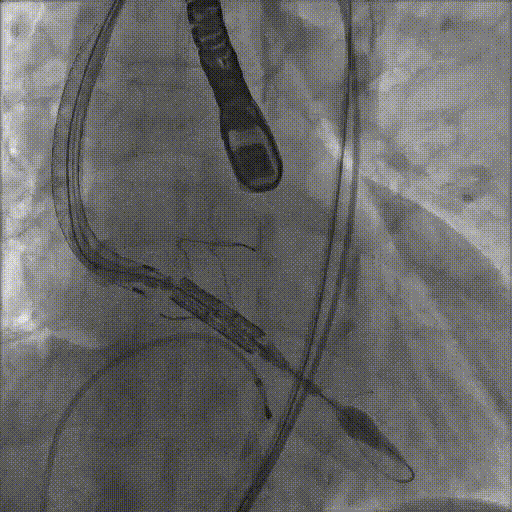

术后造影未见残余反流

手术于2022年7月13日上午10:30开始,在吴延庆教授团队操作及周达新教授远程视频指导下,于11:10手术成功完成植入,术后造影及心脏超声提示主动脉瓣无残余反流,手术成功,术后转入心脏监护室进一步观察。